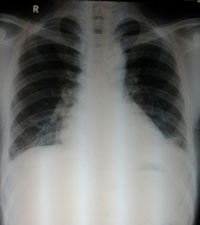

CTMTP: Bạch cầu tăng 13.000/mm3, bạch cầu ái toan chiếm ưu thế 11%, bạch cầu đa nhân trung tính 70%; chỉ số CRP: 47 mg/L (bình thường < 3); men gan AST: 88 U/L, ALT: 100 U/L, GGT: 100 U/L; men tim CK-MB, Troponin T: Âm tính; X-quang phôi: bóng tim lớn nhẹ, tràn dịch màng phổi phía bên (T); siêu âm tim: màng ngoài tim Echo kém, dày 3 - 5 mm; siêu âm bụng: Gan lách bình thường, ghi nhận TDMP (T), bề dày lớp dịch 37 mm.

Sau 3 ngày điều trị bệnh nhân vẫn còn sốt, đau ngực tăng, đau cả ngực (P) và (T). X-quang phổi kiểm tra cho thấy TDMP bên (T) tăng. Siêu âm màng phôi cho hình ảnh TDMP 2 bên. Bệnh nhân được chọc dịch màng phổi để xét nghiệm, kết quả như sau:

-X-quang phổi, siêu âm không còn dịch màng phổi.

Ngày 01/7/2014 | Ngày 08/7/2014 | Ngày 25/7/2014 |